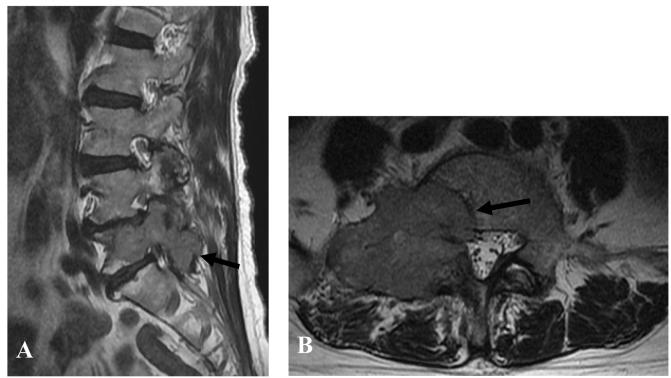

A 71-year-old woman presented to a local hospital with complaints of low back pain. Computed tomography (CT) at the hospital revealed metastases to the lung, occipital bone, right ribs and fifth lumbar vertebrae from a primary left renal cancer. A lumbar Magnetic resonance imaging (MRI) performed at local clinic revealed an enlarged metastatic tumor invading the right body, transverse process and pedicle of fifth lumbar vertebra. Transmyofascial insertion of pedicle screws and connection with rod utilizing minimally invasive surgery (MIS) systems were made on the left L4.5.S1 vertebrae under fluoroscopy. The operating time was 36 min, the intraoperative blood loss was 30 g and fluoroscopic time was 56 s. Postoperative course was uneventful. She could walk with a single cane on the twenty postoperative days but passed away of systemic metastasis approximately10 months after the spinal fixation. An x-ray taken just before death showed no spinal instrumentation failure.

一名71岁女性因腰痛就诊于当地医院。医院的计算机断层扫描(CT)显示,原发性左肾癌已转移至肺部、枕骨、右肋骨和第五腰椎。当地诊所进行的腰椎磁共振成像(MRI)显示,一个增大的转移瘤侵犯了第五腰椎的右侧椎体、横突和椎弓根。在荧光透视下,采用微创手术(MIS)系统经肌筋膜在左侧L4、5、S1椎体置入椎弓根螺钉并连接棒。手术时间为36分钟,术中失血30克,透视时间为56秒。术后过程顺利。术后20天她可以单拐行走,但在脊柱固定后约10个月因全身转移去世。临终前拍摄的X线片显示脊柱内固定无失败。